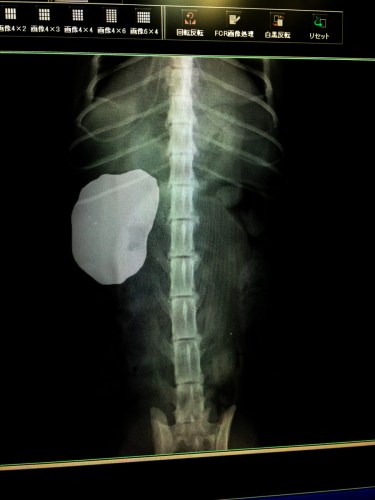

うおっほ、これがだいずさんのレントゲン写真です

いや全く無い訳ではありませんが3年前の写真と比べると明らかに左側が萎縮してます

その代わり動いている右側が肥大してフル稼働しているようです

だいずさんは生まれ付き左側の腎臓が機能不全と考えられます